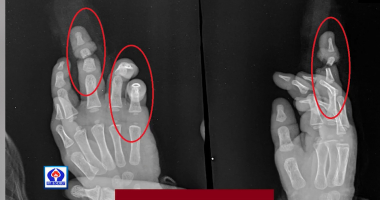

8 տարեկան երեխան փայտ է կտրել ու վնասել 2 տարեկան եղբոր...

8 տարեկան երեխան փայտ է կտրել ու վնասել 2 տարեկան եղբոր մատները: Այս սեզոնին ավելացել են անդամահատված մատների դեպքերը: Վերջին շրջանում «Սուրբ Աստվածամայր»...